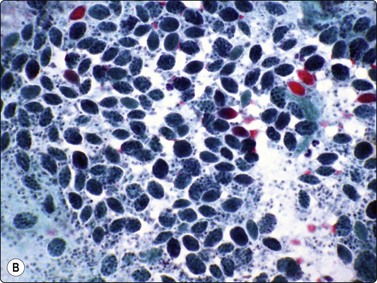

Negative images of mycobacteria may be seen in the background serum and cytoplasm of histiocytes in the Giemsa stain (Fig. 18.5), and the beaded 3–4-micron bacilli stain in the ZN (Fig. 18.6A) and auramine (Fig. 18.6B) stains and autoflouresce in the Papstain.41

image image

Fig. 18.6 (A) Curved beaded mycobacteria in Ziehl Neelsen stain (ZN, ×1000); (B) Mycobacteria in Auramine stain (Auramine, ×1000).